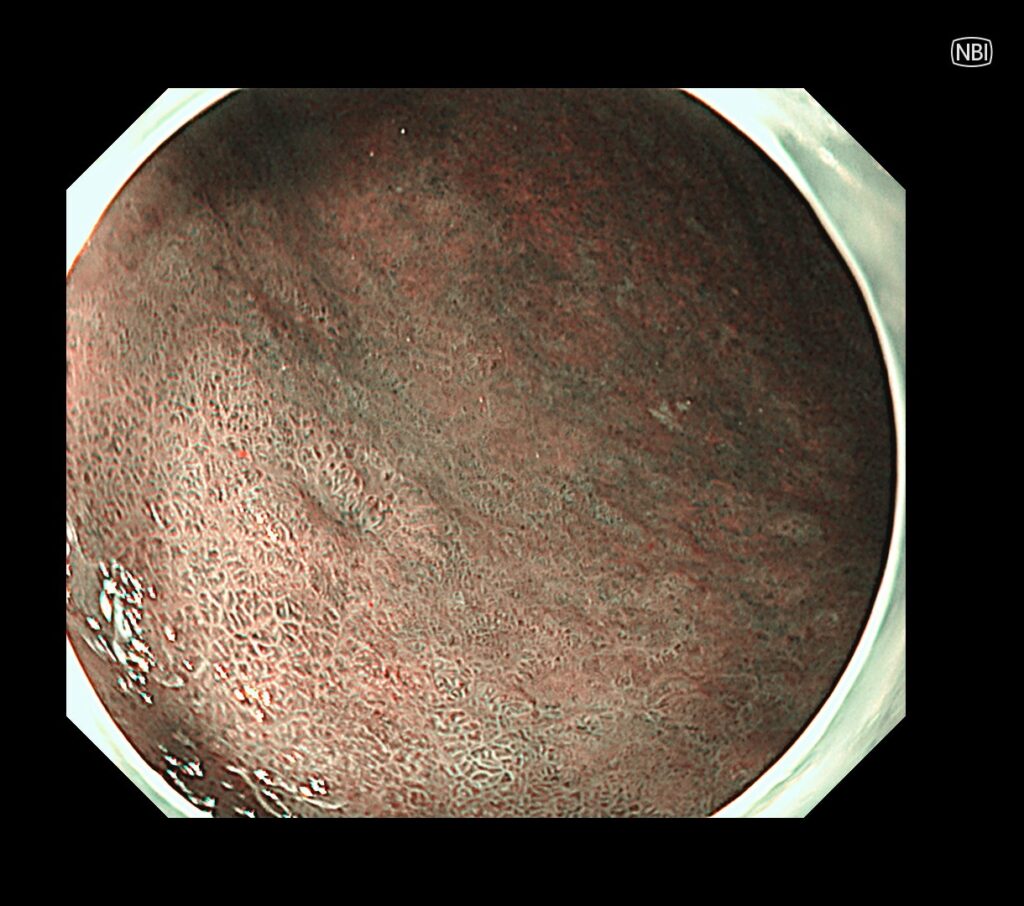

今回の病変は、NBIモードより、上述したTXIモードのほうが癌の視認がしやすい病変です。

ただし、癌の範囲診断は、NBIのよる拡大観察が優れています。

拡大観察すると、やや凹んだ部位(陥凹部)に一致して、領域(境界明瞭)のある癌がわかるかと思います。